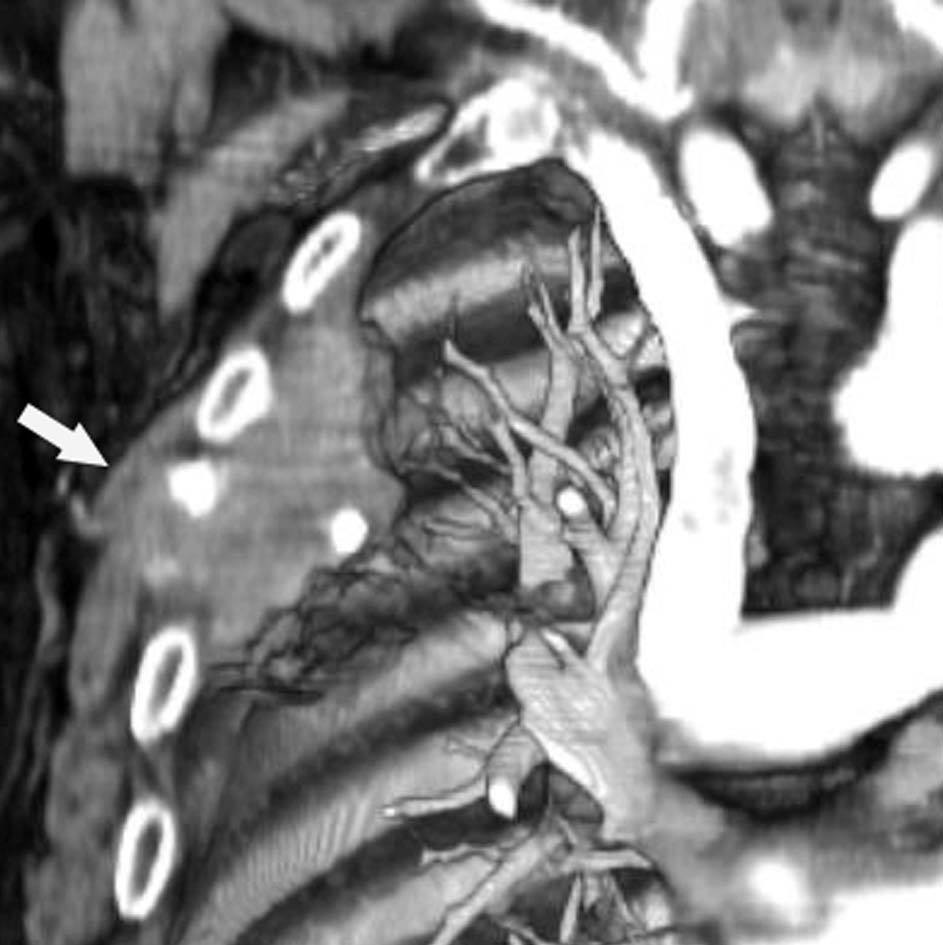

Pese a las conocidas limitaciones de la TC, ésta continúa siendo la técnica de elección en la estadificación del tumor en los pacientes con CPNM; su sensibilidad y especificidad en la determinación de la infiltración de pared oscilan entre el 38 y el 87% y del 40 al 90%, respectivamente, según las series. El desarrollo de nuevos equipos de TC helicoidal y principalmente las TC multidetectoras (TCMD) proporcionan unas imágenes 2D de mayor resolución con la posibilidad de hacer reconstrucciones multiplanares (MPR) en distintos planos del espacio e incluso 3D con la consiguiente mejora de la valoración del tumor, su extensión e infiltración de estructuras vecinas5 (fig. 4). Así, con la TCMD se puede poner de manifiesto con mayor fiabilidad la invasión de la cisura, la pared torácica o el mediastino, y además es capaz de determinar, gracias a las reconstrucciones de volumen, la relación exacta del tumor con la vía aérea (fig. 5). El progreso en la capacidad diagnóstica deriva del incremento en la resolución de las imágenes obtenidas y de la posibilidad de emplear nuevas aplicaciones como la broncoscopia virtual y la visualización en tiempo real. La broncoscopia virtual es útil para valorar la invasión del árbol traqueobronquial con la finalidad de planificar la cirugía, también como guía para el fibrobroncoscopista y, por último, porque permite ver el árbol bronquial distal a la estenosis (fig. 6)6. La capacidad de ver la imagen en tiempo real es especialmente útil cuando se emplea como guía en maniobras intervencionistas como biopsias percutáneas, ya sea con finalidad diagnóstica o como parte de la estadificación (fig. 7). Esta técnica de guía de biopsia denominada TC fluoroscopia reduce el número de pases y el tiempo global de la exploración, implica un menor riesgo de lesión de estructuras y permite la visualización inmediata de las posibles complicaciones7.

La precisión de la TC para predecir la afectación ganglionar mediastínica, pese a la ayuda que suponen las reconstrucciones MPR y 3D en la valoración de determinados territorios ganglionares (espacio subcarinal, hilio o ventana aortopulmonar) (fig. 11), sigue teniendo muchas limitaciones. El único criterio que se emplea para considerar que un ganglio es patológico es el tamaño (cuando el eje corto es mayor de 10 mm, salvo en el espacio subcarinal que se acepta hasta 12 mm). El empleo únicamente de criterios de tamaño hace que la TC sea una técnica poco precisa en la valoración de la afectación ganglionar. En un metaanálisis reciente13 la sensibilidad global de la TC para estadificar el mediastino fue de un 57%, con una especificidad del 82%, un valor predictivo positivo (VPP) del 56% y un valor predictivo negativo (VPN) del 83%. Lo que es innegable es la capacidad de la TC para mostrar un mapa de los ganglios tanto hiliares como mediastínicos (fig. 12), lo cual es de gran utilidad en la determinación del factor N. La valoración del territorio hiliar puede ser compleja por la agrupación de estructuras vasculares, por lo que además de la opacificación adecuada de éstas, es de utilidad la identificación de la pérdida del ángulo de la bifurcación (carina secundaria), ya que el eje corto significativo en este territorio es de 3 mm. Como ya hemos comentado, también es de gran ayuda en esta localización el empleo de reconstrucciones (fig. 11)5.